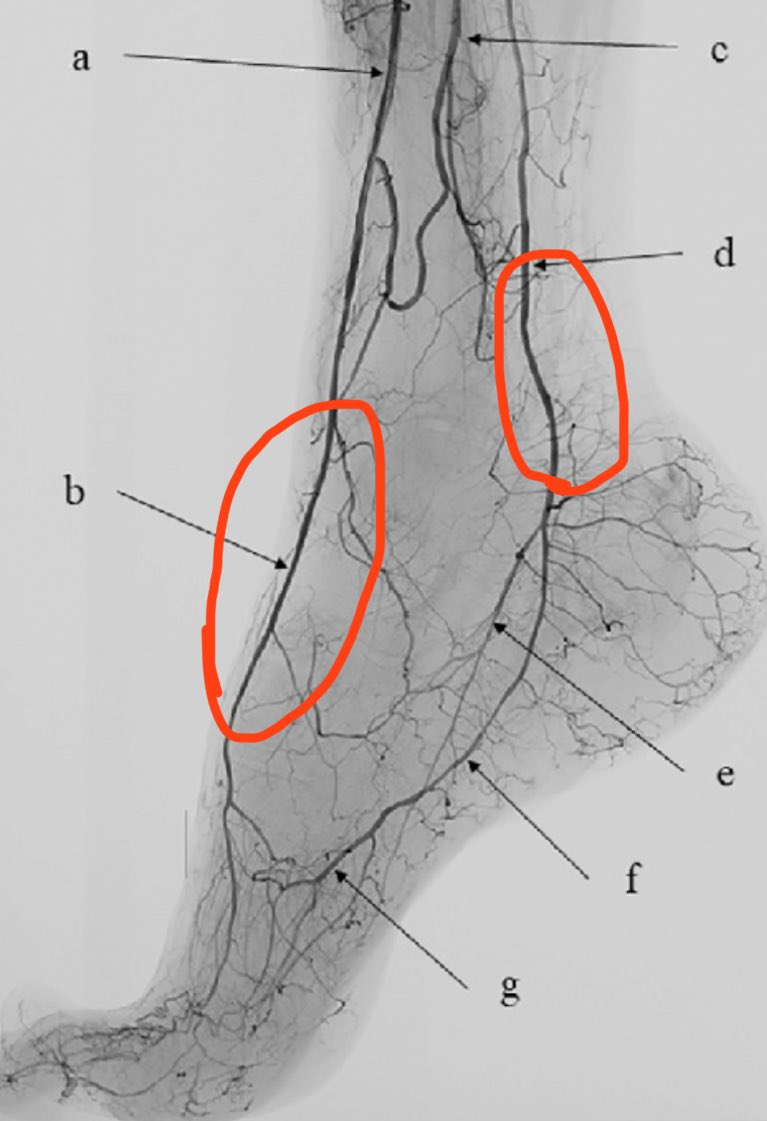

٨- لكي نبسط الفكرة، لنأخذ قدم الانسان كمثال. هذه الصورة توضح شرايين القدم بالقسطرة. لاحظ كمية التفاصيل الدقيقة الممكن ملاحظتها. لكن بدون القسطرة يتم فحص الشرايين بالدوبلر (عبارة عن أشعة صوتية). لكن ، لا يمكن للدوبلر الا التعرف وفحص الشرايين الكبيرة (غالباً شريانين فقط كما نو موضح بالأحمر). باقي الشرايين الصغيرة؟ لا يمكن. فمحدودية قدرات الدوبلر معروفة (اشعة صوتية) وإن اختلف الحجم.

٩- عند القيام بعملية الربط لدوالي الخصية الجراحي يتم التعرف على الشريان الأساسي (لاحظ مقاطع سابقة غرّد بها القلة من ناشرين المعلومات المغلوطة - الحديث دائماً عن "شريان" الخصية) وعزله (الابتعاد عنه) وربط الدوالي. ماذا عن البقية؟ الافرع الصغيرة؟ الشعيرات الأصغر؟

١١- الدراسات كثيرة فيما يخص عدد الشرايين التي تم التعرف والابقاء عليها جراحياً. الدراسات تذكر ان في غالبية الحالات يتم المحافظة على شريان واحد ، وفي حالات اقل يتم المحافظة على اثنين ، وفي حالات نادرة جداً يتم المحافظة على ثلاث شرايين!